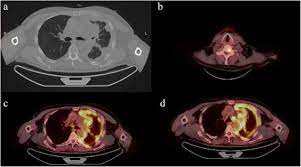

Early detection of the fatal and incurable mesothelioma and the later provision of radiation, surgical and palliative asbestosis treatments are known to help a patient to have the best possible chance to extend and enhance the quality of life remaining. Provide pertinent illustrative figures of pet/ct and ct for malignant pleural mesothelioma. This retrospective study aimed to investigate the prognostic value of the suvmax in patients with mpm. European journal of nuclear medicine and molecular imaging, 2014. pet/ct scan problem of pleural effusion therapy for mesothelioma sufferers early detection of the deadly and incurable. He underwent vats with pleural drainage, biopsy and extensive decortication. These imaging tests will show visual evidence of mesothelioma. Pathology revealed epithelioid type malignant mesothelioma involving parietal and visceral pleura with clear margins (stage pt1bn0).

European journal of nuclear medicine and molecular imaging, 2014. Given the presence of the mesothelium in different parts of the body, mesothelioma can arise in various locations 17:. At left is a ct scan, while the center image is a pet scan. Sensitivity, specificity and accuracy were respectively 86, 89 and 87%; The tumor originates from cells of the visceral or parietal pleural and is linked to asbestos exposure with a median latency of 44.6 years .due to the latency between exposure and onset of mesothelioma and the ongoing use of asbestos in parts of the world, the incidence is expected to rise. Current perspectives maria bonomi,1 costantino de filippis,2 egesta lopci,3 letizia gianoncelli,1 giovanna rizzardi,4 eleonora cerchiaro,1 luigi bortolotti,4 alessandro zanello,2 giovanni luca ceresoli1 1department of oncology, thoracic and gu oncology unit, 2department of radiology, cliniche humanitas gavazzeni, bergamo, 3nuclear medicine. Kazuhiro kitajima, hidetoshi matsuo, atsushi kono, kozo kuribayashi, takashi kijima, masaki hashimoto, seiki hasegawa, takamichi murakami, koichiro yamakado. The qualitative assessment was statistically different (p=0.0020, χ). Have been diagnosed with mesothelioma, your doctor may use this test to see if the cancer has spread to lymph nodes or other parts of the body. pet scans are often paired with ct scans to provide doctors with the most accurate view of a patient's body: A tissue biopsy will finalize whether or not a patient has this cancer. It can help identify the best therapies to control the cancer while maximizing quality. When a ct scan is performed, patients may also undergo a pet scan.

191 all treatments were planned based on ct and pet/ct imaging. Given the presence of the mesothelium in different parts of the body, mesothelioma can arise in various locations 17:. pet/ct scan problem of pleural effusion therapy for mesothelioma sufferers early detection of the deadly and incurable. A pet scan is the best method to determine if mesothelioma has spread to other parts of the body. pet/ct did not show any abnormal fdg uptake in the right pleura or remainder of the chest.